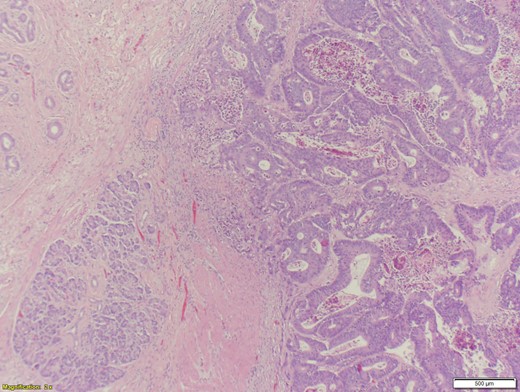

A 70-year-old female presented to the emergency department with complaints of diarrhea, vague, dull abdominal pain, unintentional weight loss and poor appetite. No hematochezia or melaena stated. Fecal occult is strongly positive in the ED. No endoscopies were found in her records. PMHx included COPD, osteoarthritis and DVT. Significant physical exam findings included mild, diffuse abdominal tenderness and RUQ palpable mass, and normal bowel sounds. Labs were significant for a hemoglobin of 5.7, hematocrit of 18.6% and CEA of 29.6. An abdominal/pelvis CT exhibited a 6 cm circumferential mass of the hepatic flexure (Figs 1–3). Two days later, a right hemicolectomy with en bloc pancreaticoduodenectomy was performed. Pathology showed adenocarcinoma stage IIIc (Figs 4–10). Post-operatively, an abdominal/pelvis CT showed bilateral pulmonary emboli and a 14 cm pelvic abscess. Bilateral lower extremity ultrasound showed low probability for DVT. Exploratory laparotomy was performed where the pelvic abscess was seen and extensive lysis of adhesions, resection of ileocolonic anastomosis for contained leak and ileostomy performed. Approximately 4 months after discharge, the patient passed away while in a long-term care facility.